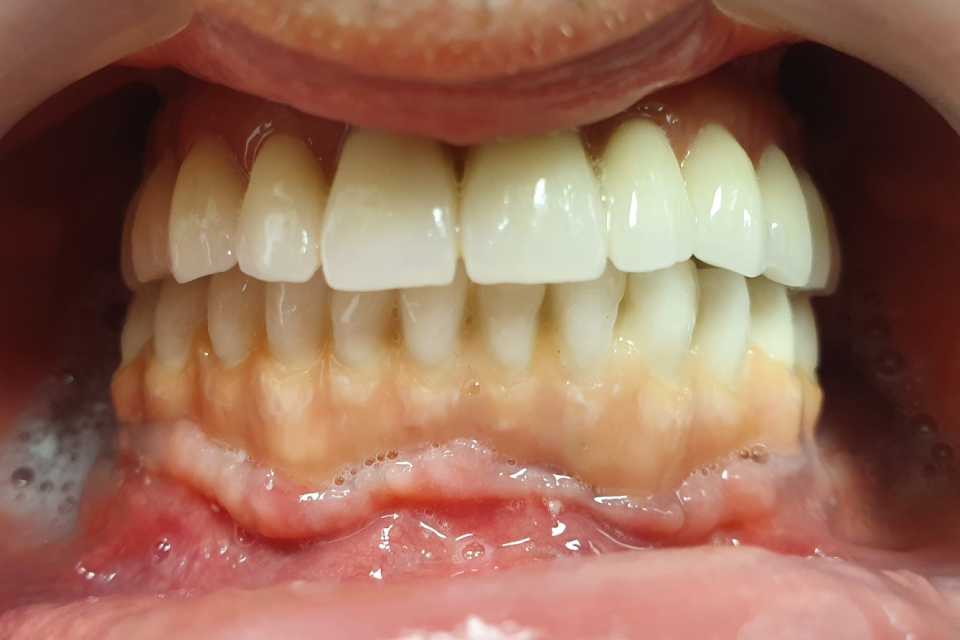

Pacientul a revenit in cabinet pentru consultatia anuala de intretinere, implanturile fiind inserate in urma cu 5 ani.

Cazul a fost unul foarte dificil pacientul fiind purtator vechi de proteze totale acrilice bimaxilar. A fost nevoie de 2 sinus lifting-uri si 5 implanturi pentru arcada superioara, iar pentru arcada inferioara s-au realizat aditii osoase (bilateral), prin tehnica Khoury.

Rezultatele au fost spectaculoase, fara sa fi intervenit resorbtii de natura osasa sau gingivala, pacientul fiind foarte multumit.